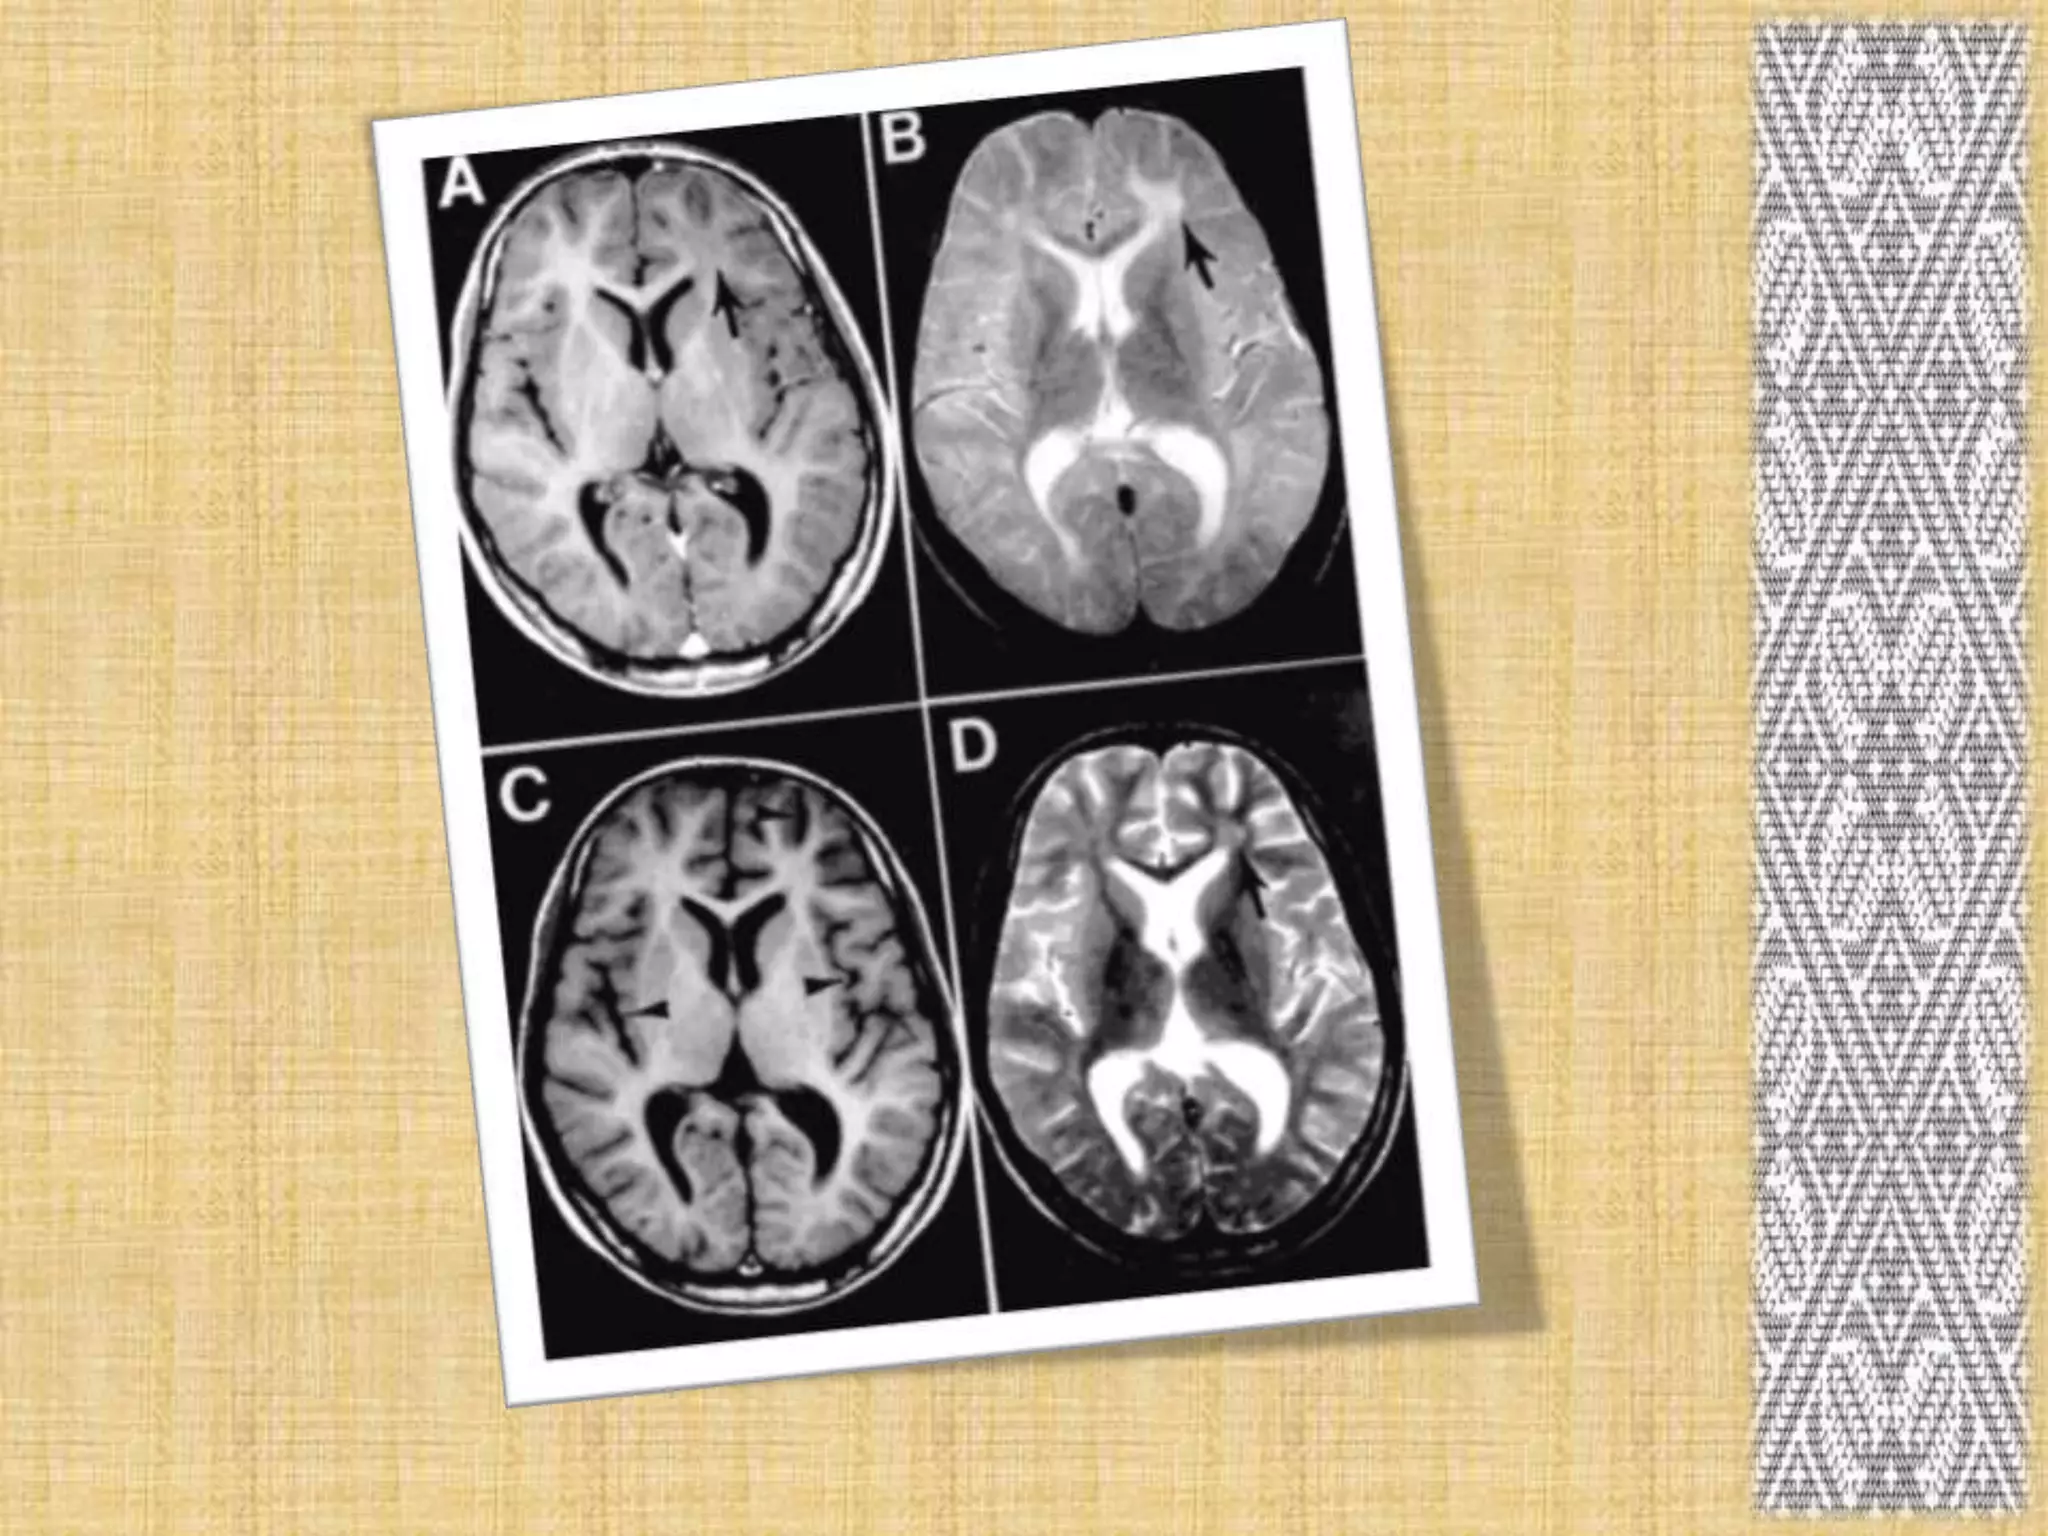

Brain MRI.

diagnosis There may bea history of measles in an unvaccinated child. A physical examination may reveal: Damage to the optic nerve, which is responsible for sight Damage to the retina, the part of the eye that receives light Muscle twitching Poor performance on motor (movement) coordination tests. The following tests may be performed: Electroencephalogram (EEG). Brain MRI. ELIZA. Spinal tap.